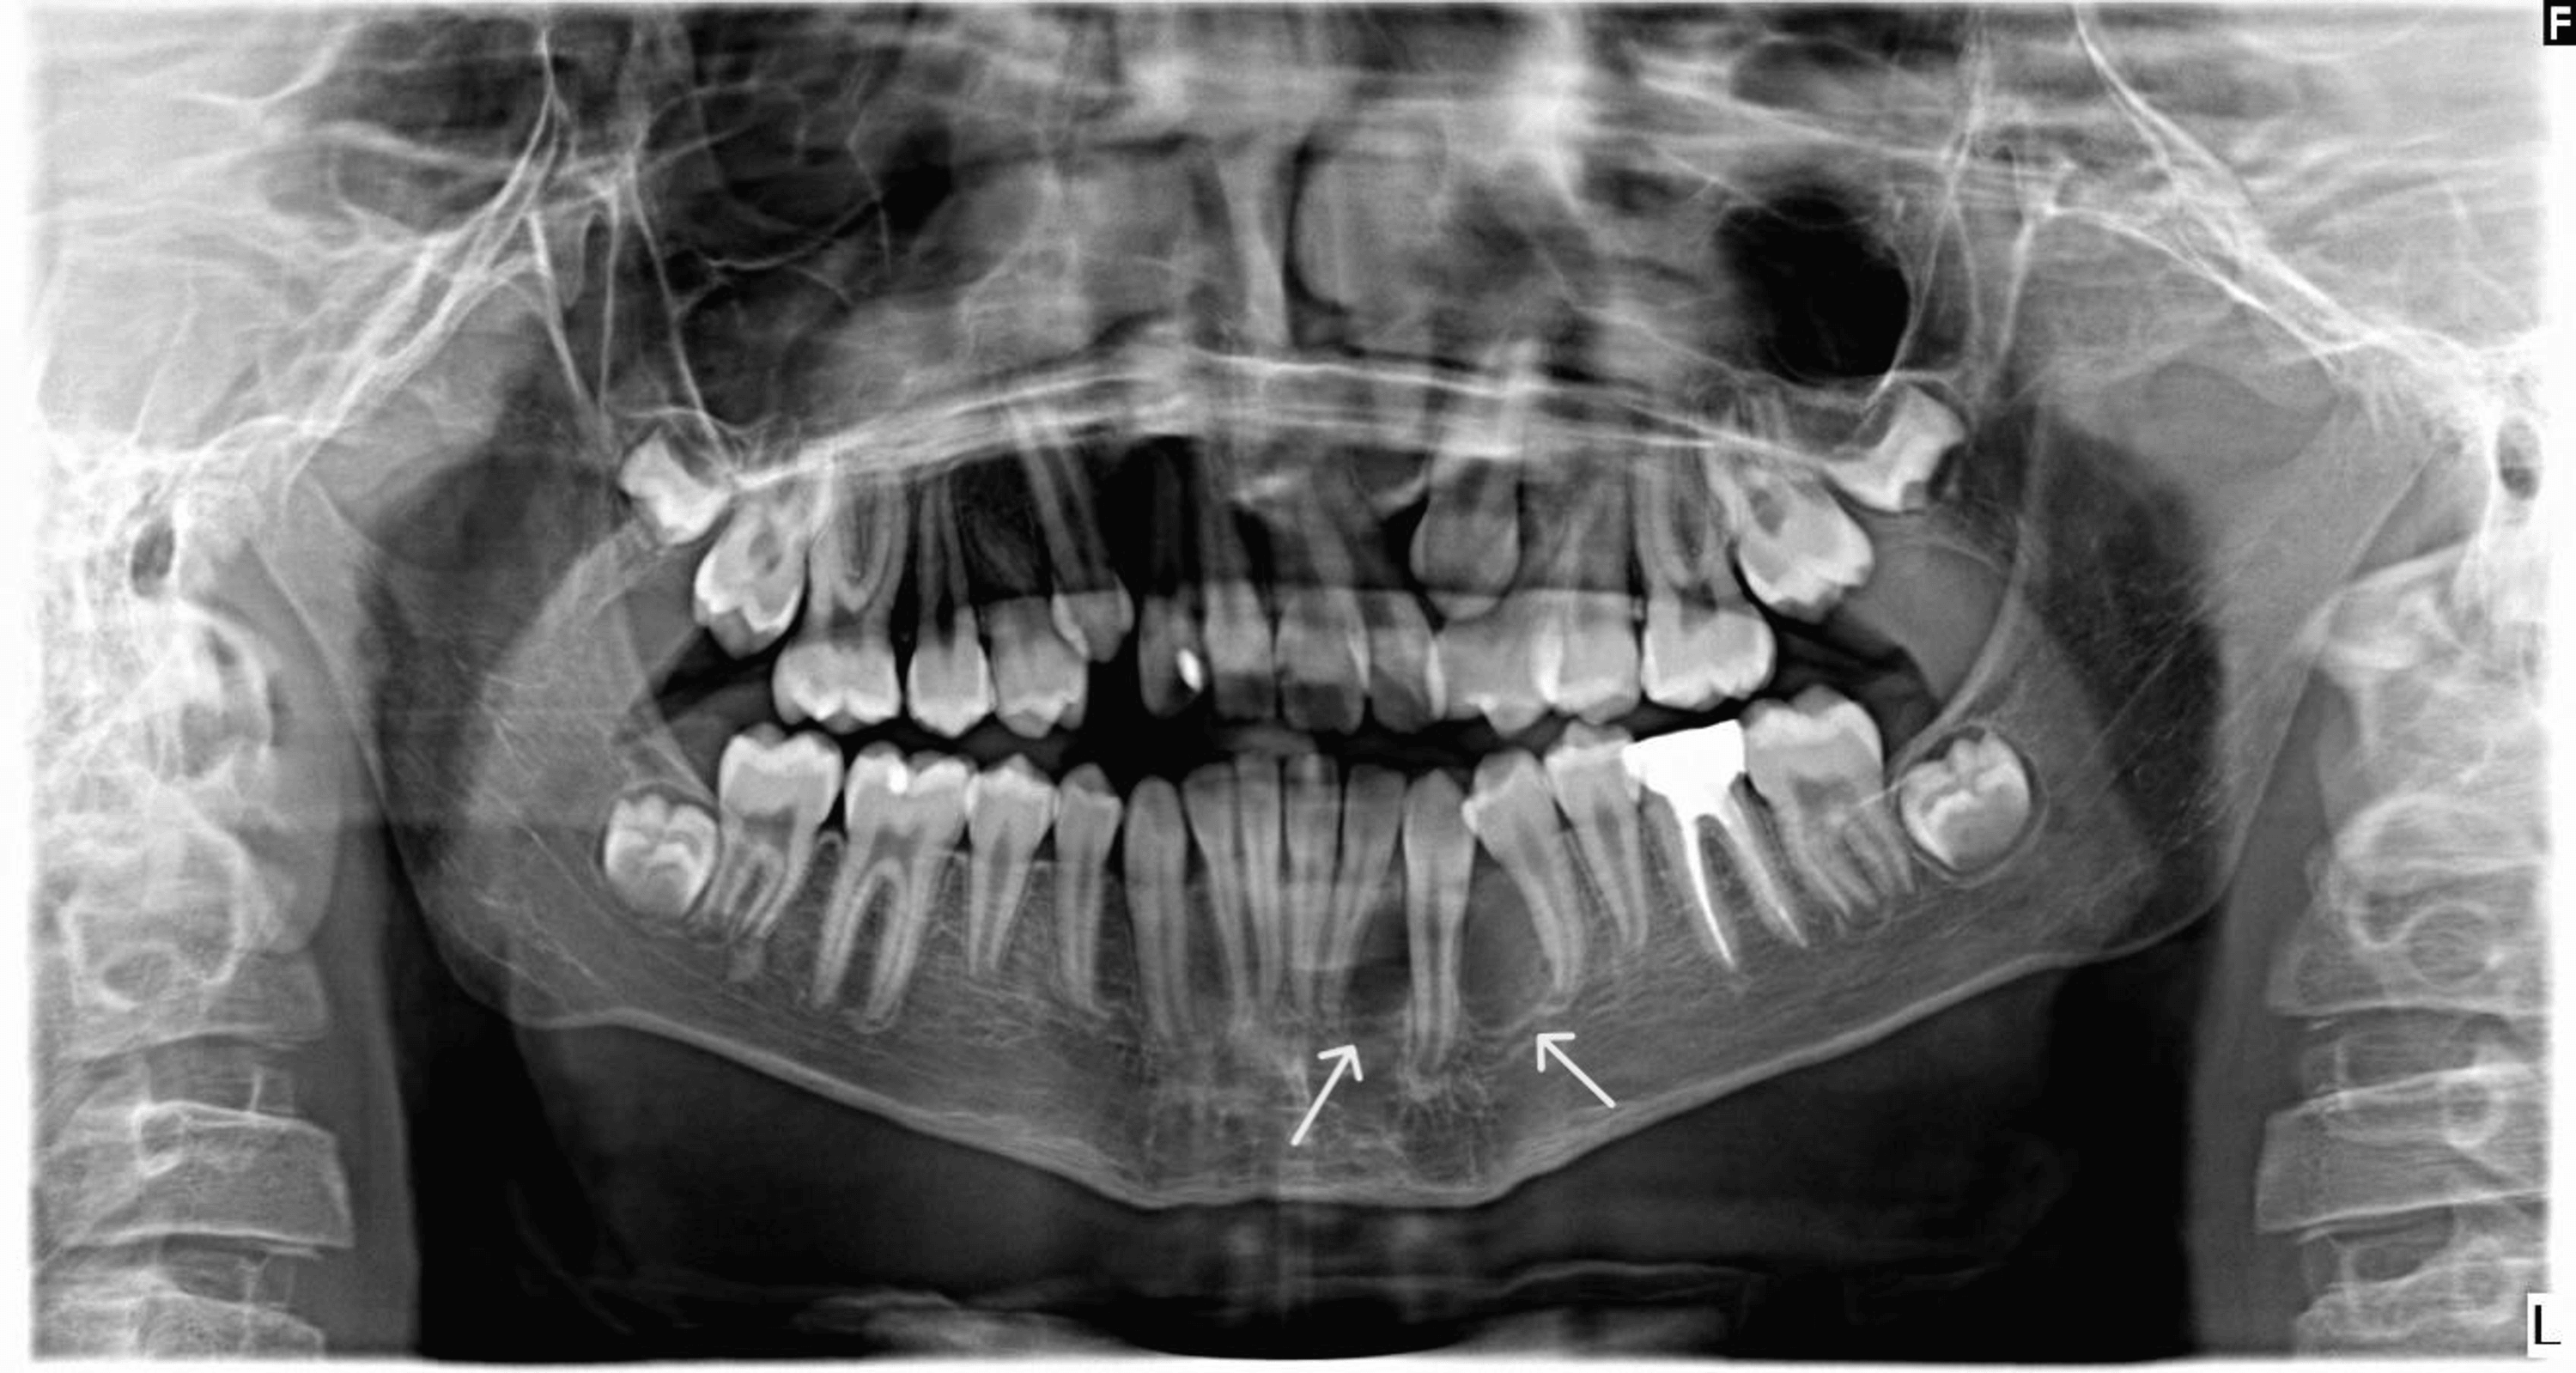

Maxillary Odontogenic Keratocyst . — the odontogenic keratocyst (okc) is one of the most aggressive odontogenic cysts. odontogenic keratocysts (okc), previously known as keratocystic odontogenic tumors (kcot or kot), are rare benign cystic lesions involving the mandible or. The main difference between okcs and other jaw cysts. — an odontogenic keratocyst (okc) is a benign but aggressive intraosseous tumor derived from the. — odontogenic keratocysts (okcs), first described by philipsen in 1956 [1], are benign intraosseous lesions of. figure 5 odontogenic keratocyst between roots of right maxillary incisors (circled by white dots). — odontogenic keratocysts (okc), previously known as keratocystic odontogenic tumours (kcot or kot), are. — the odontogenic keratocyst (okc) is one of the most aggressive odontogenic cysts.

— odontogenic keratocysts (okcs), first described by philipsen in 1956 [1], are benign intraosseous lesions of. figure 5 odontogenic keratocyst between roots of right maxillary incisors (circled by white dots). The main difference between okcs and other jaw cysts. — an odontogenic keratocyst (okc) is a benign but aggressive intraosseous tumor derived from the. odontogenic keratocysts (okc), previously known as keratocystic odontogenic tumors (kcot or kot), are rare benign cystic lesions involving the mandible or. — the odontogenic keratocyst (okc) is one of the most aggressive odontogenic cysts. — odontogenic keratocysts (okc), previously known as keratocystic odontogenic tumours (kcot or kot), are. — the odontogenic keratocyst (okc) is one of the most aggressive odontogenic cysts.

Maxillary Odontogenic Keratocyst The main difference between okcs and other jaw cysts. — an odontogenic keratocyst (okc) is a benign but aggressive intraosseous tumor derived from the. The main difference between okcs and other jaw cysts. — odontogenic keratocysts (okc), previously known as keratocystic odontogenic tumours (kcot or kot), are. — the odontogenic keratocyst (okc) is one of the most aggressive odontogenic cysts. — the odontogenic keratocyst (okc) is one of the most aggressive odontogenic cysts. — odontogenic keratocysts (okcs), first described by philipsen in 1956 [1], are benign intraosseous lesions of. odontogenic keratocysts (okc), previously known as keratocystic odontogenic tumors (kcot or kot), are rare benign cystic lesions involving the mandible or. figure 5 odontogenic keratocyst between roots of right maxillary incisors (circled by white dots).